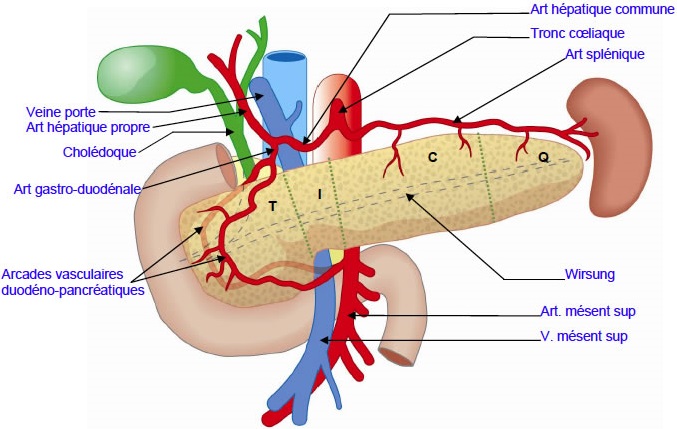

Rappel anatomique du pancreas

Le pancreas se situe fixe , en profondre

retroperitoine de l'abdomen en avant des gros vaisseaux et

s'allonge en un axe oblique en haut , a gauche au hile

splenique .Sa tete est en concave et recouvre entre 12 eme

vertebre thoracique a la 3eme vertebre lombaire . En

classiquement il en segmente en 4 parties : la tete ,

l'ishme , le corp et la queue .

- La tete , partie la plus large ,

situe a interieure du cadre duodenale , en

limite en haut par pedicule hepatique , a

droite par le duodenum et a gauche par les

vaisseaux mesenterique . Le crochet ( petite

pancreas de winslow) est un prolongement de

la tete a sa partie inferieure |

- L'ishme : situe

avant de flexus mesenterico-porte et se

projette legerement a droite de la ligne

mediane . . |

- Le corps est oblique a gauche ,

en arriere et vers le haut , aplati

antero-posterieure . |

- La queue en direction vers le

hile de la rate et en croissement du bord

superieure par artere splenique |

Vascularisation du pancreas : La vascularisation

du pancreas est en triple provenir de artere gastroduodenale

AGD , artere mesenterique superieure AMS et artere splenique

. On en divisie en deux reseaux principale :

la vascularisation cephalique

comporte des arcade pancreatico -duodenale anterieure et

posterieure , branche des 4 arteres pancreatico-duodenale (

ADP ) figure 01 . La

vascularisation corporeocaudale s'effectue par

artere splenique penetre dans la parenchyme du pancreas et

anastomose avec artere pancreatique inferieure une branche

de artere mesenterique superieure . Le retour veineuse

cephalique est assure par 4 veine pancreatico duodenale (VPD

) et sa branche postero-superieure abouchement direct au

bord droit de la veine porte . La VPD antero -superieure

abouche dans le tronc veineuse gastrocolique de Henle.